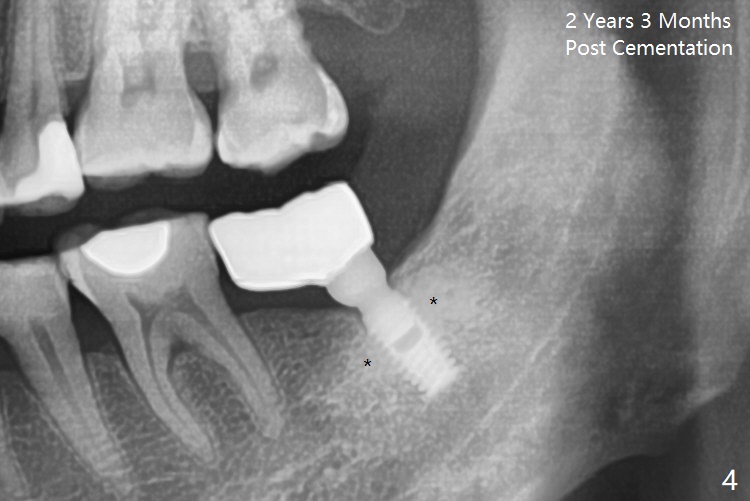

Implant Placed for Opposing Tooth Intrusion

A 4.5x8 mm Bicon implant is placed (Fig.1-3) with intent to intrude the supraerupted opposing tooth once a provisional is fabricated. Now it is 5 months postop. In spite of poor implant position, the abutment or the crown has not become loose with increased bone density around the implant 2 years 3 months post cementation (Fig.4: *). Guide could easily overcome the deficiency.